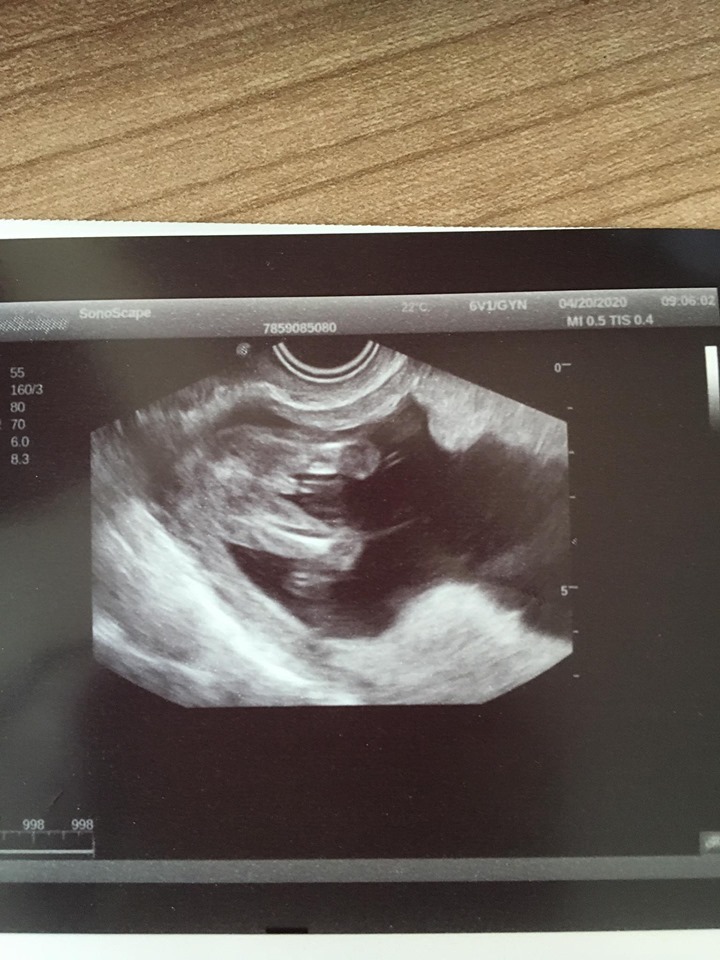

Já jdu zítra na druhý screen 🥰🥰🥰🥰 a asi si nechám říct pohlaví. Budu začínat 21tt 🤦♀️😁 strašně to utíká.